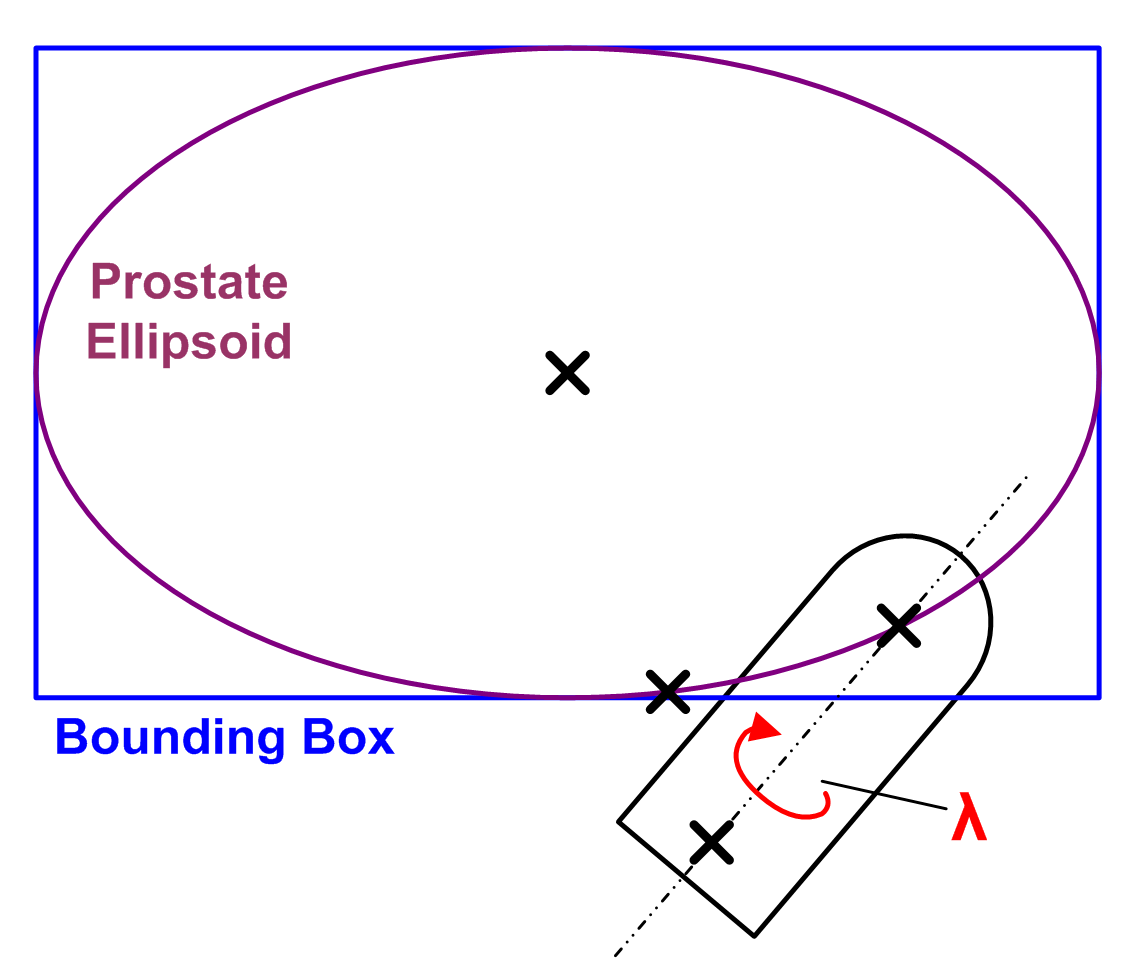

With these assumptions it is possible to define a probe movement model based on a prostate surface approximation, the probe position in the US image (which is known) and a rotational fixed point in the rectum. As shown in Fig. 1, the prostate surface is approximated by a bounding-box aligned ellipsoid. The ellipsoid is modeled using a 2D polar parameterization . The origin of the parameterization corresponds to the intersection of the line from the prostate center to . As illustrated in Fig. 1, implements assumption 1) by determining plausible US transducer positions on the prostate surface. Assumption 3) is satisfied by requiring that the principal probe axis must always pass through . Finally, a rotation about the principal probe axis implements assumption 2) and thus adds a third DOF (See Fig. 1).